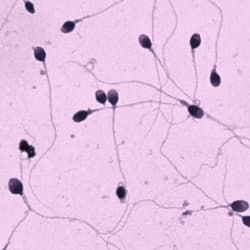

Motility

Tracks, velocities, classification

Counts and % counts: total count, motile, progressive motile, rapid/medium/slow/static classification. Mean velocities: VAP, VCL, VSL, and related metrics (per manufacturer listing). Track overlay for movement visualization. Dose calculation. Read from image sequences in different formats (bmp, tiff, jpeg, etc.). Generate comprehensive statistics for one or several fields; transfer results to Microsoft Excel; custom report generator with results and images; slow-motion playback of stored sequences for behavioral studies.